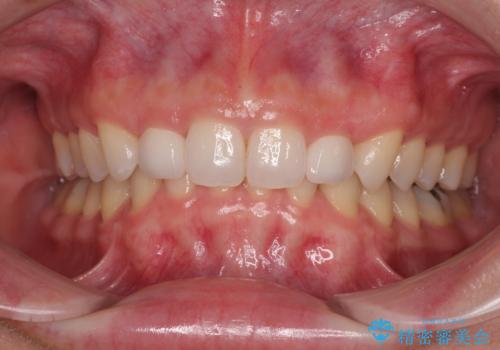

捻れて前に出ている前歯 ワイヤー装置での非抜歯矯正